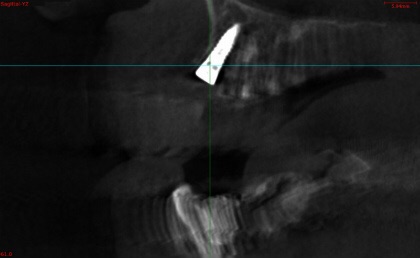

• インプラント